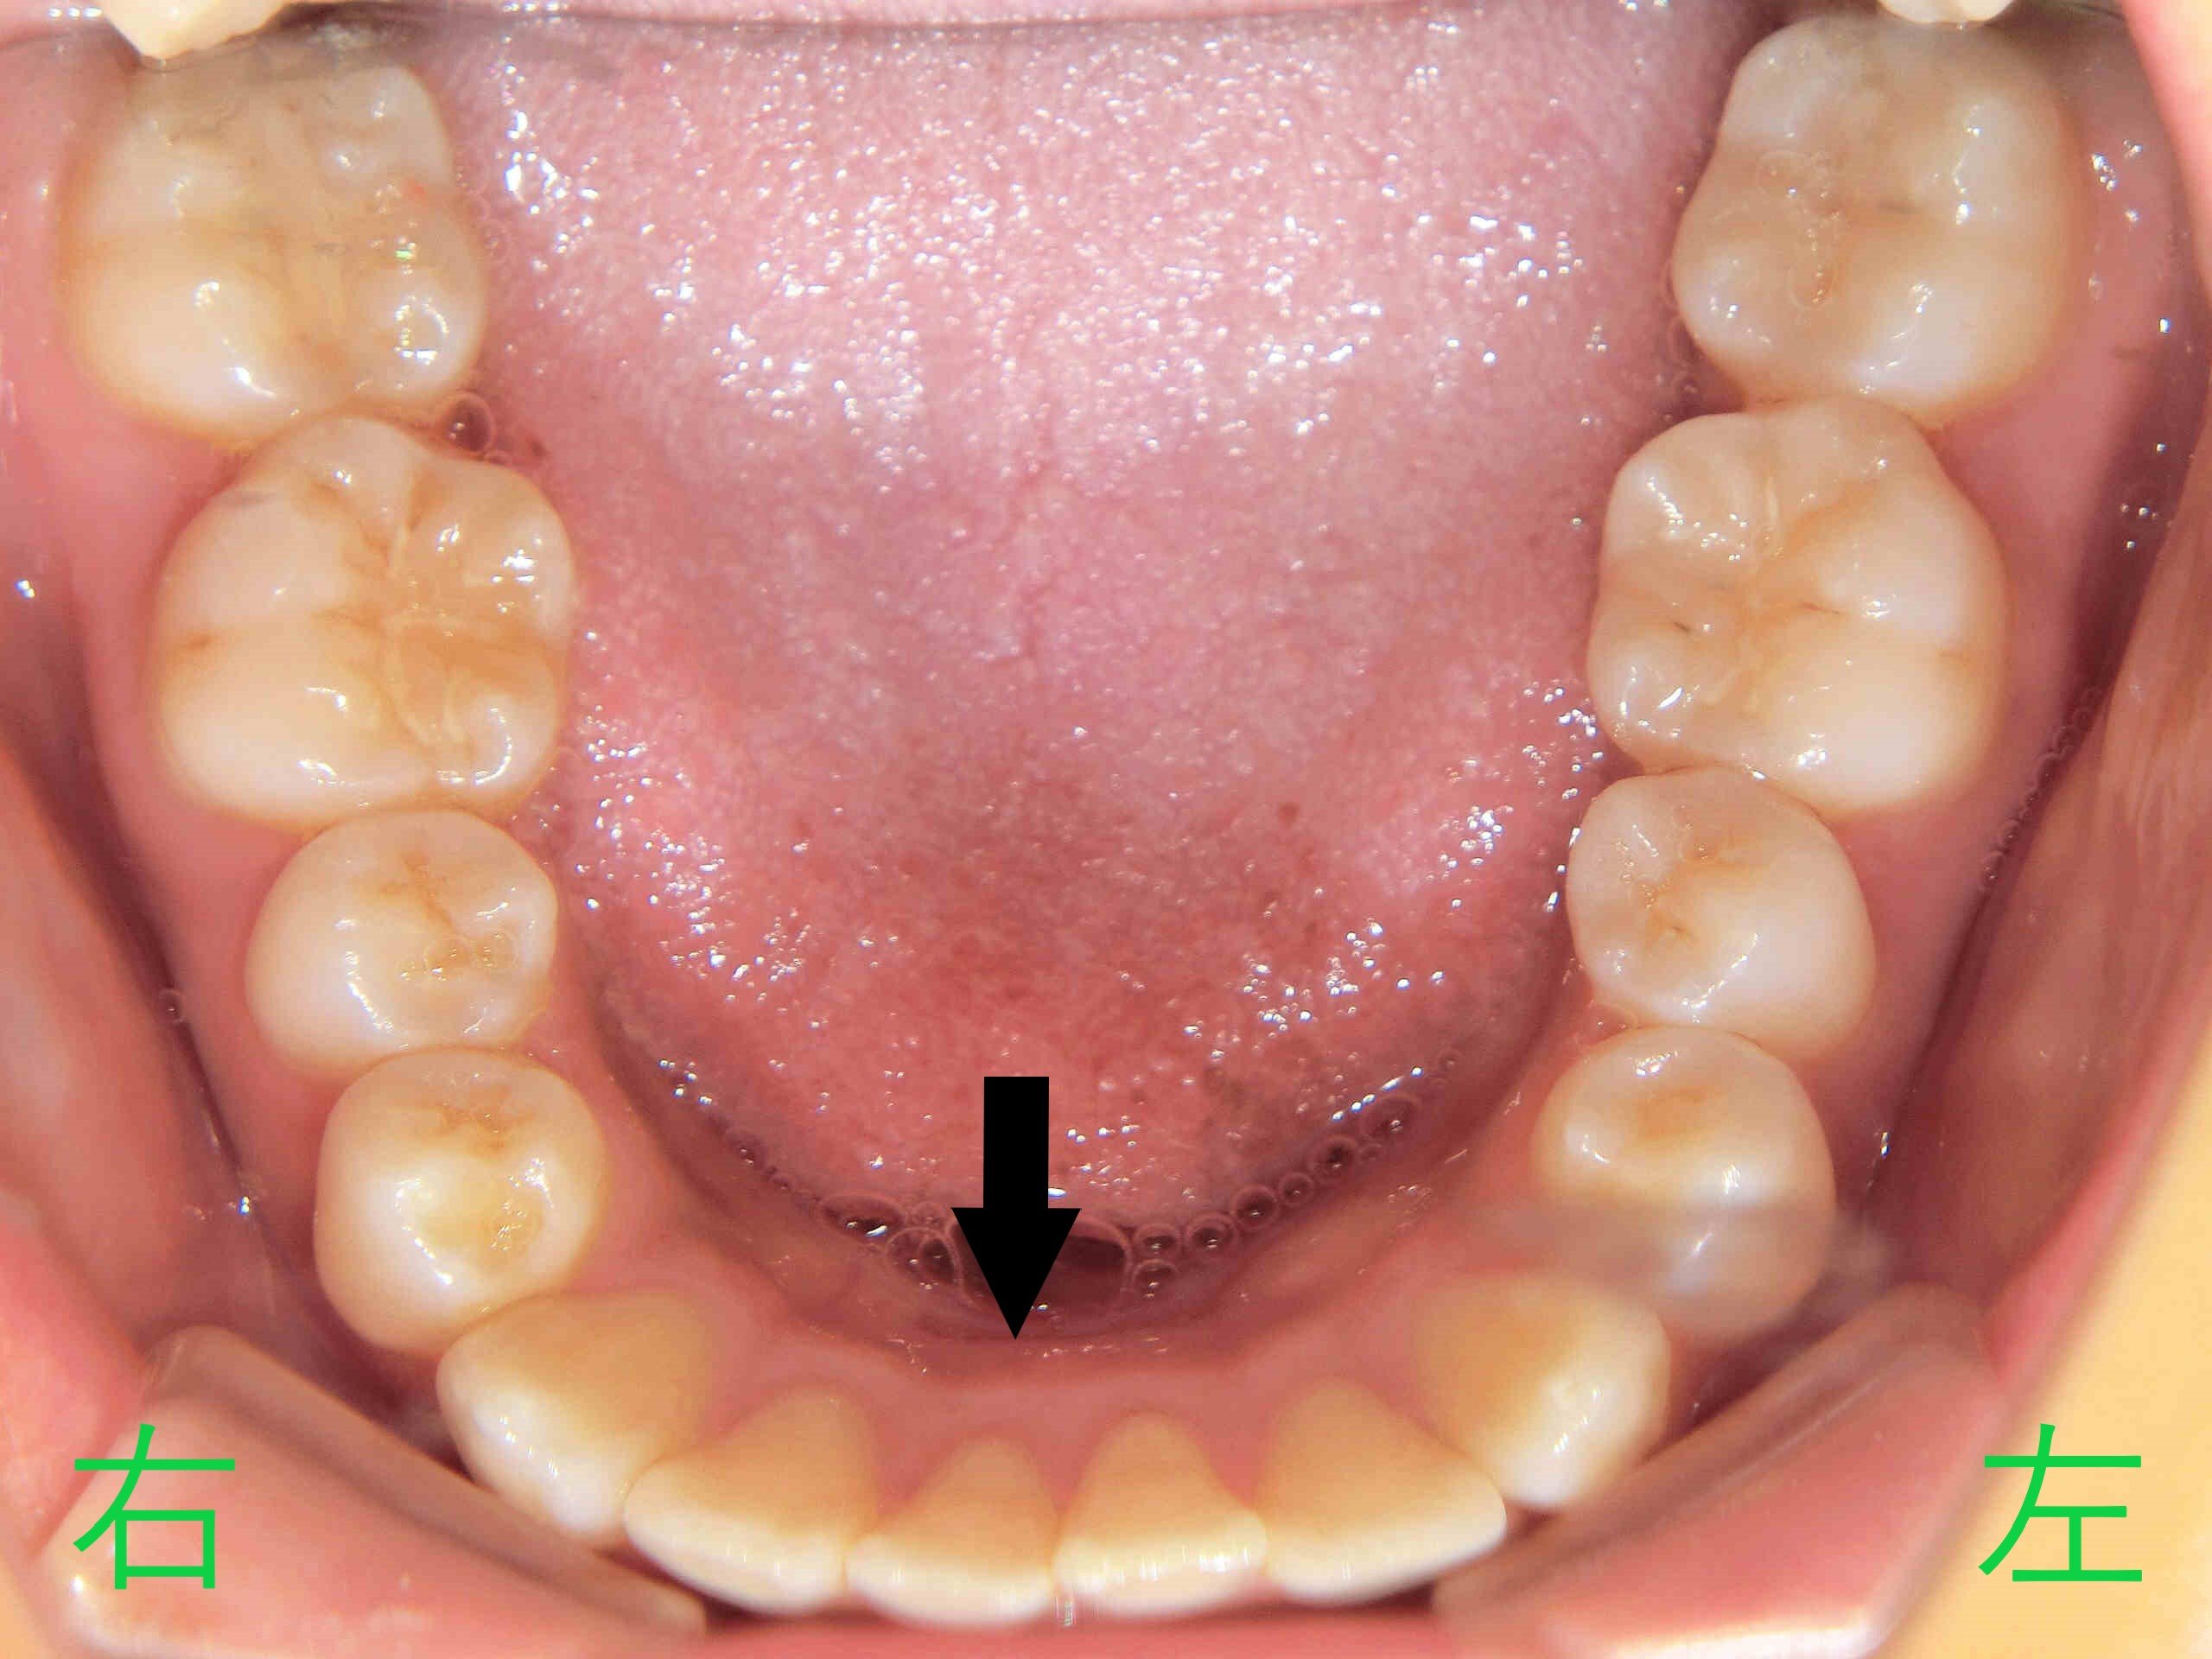

写真は前歯の噛み合わせを下から見上げたもので、上顎左右中切歯が前方に出ており、左右側切歯が内側に位置していることが確認できます。

左上の写真は上顎を下から、右上の写真は下顎を上から撮影したものです。右上の黒色矢印部分では、下顎前歯がやや前方へ傾斜している様子が見受けられます。

診断の結果、上下顎ともに矯正が必要との判断となりました。これは、上顎前歯の裏側で下顎前歯が接触している状態では、上顎前歯を後退させるためには、下顎前歯も後方に移動させる必要があるためです。